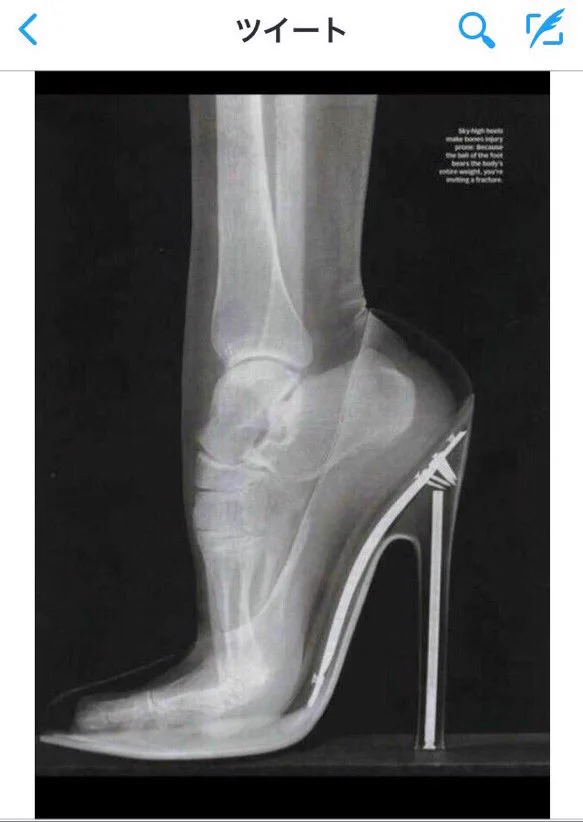

ハイヒールのレントゲン爪先立ちすぎ!でも、これ自業自得じゃないの…?www

おしゃれに我慢はつきものという言葉を女性の方はよく耳にすると思いますが、これは自己満足の範疇であるという画像が今ネットで話題になっています。どんな高さのヒールを履こうが個人の自由ですけどね…。なんだかちょっと物言いがえらそうな女性に注目しつつ、速攻で足がつりそうなレントゲン写真をどうぞご覧下さい!

個人の自由で履いているものに対して「痛いし歩きにくいから気を使え」っていうのはちょっと違うんじゃないかなーと思います。相手に強要されているならともかく、自己満足で履いているわけなのですから。ほんと、痛いならスニーカーを履けばいいのです。私は女性ですが、山坂の多い場所なのでこんなヒール履いたらすぐに足首だめにしそうです。スニーカー最強。気を使ってくれる男性は魅力的ですが、それを当たり前と思わず、まずは自分から相手に気を使えるようになると素敵な女性になれますよ~。